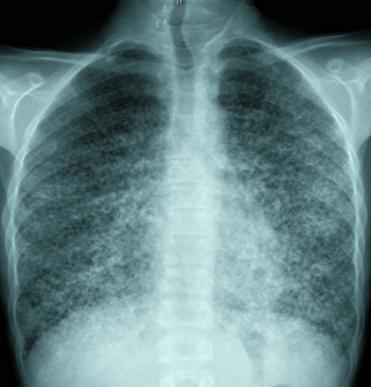

Acute bilateral airspace opacification is a subset of the larger differential diagnosis for airspace opacification. An exhaustive list of all possible causes of acute bilateral airspace opacities is long, but a useful way to consider the huge list is by the material within the airways:

(acute pulmonary edema)

B: bat-wing distribution- Bat’s wing or butterfly pulmonary opacities refer to a pattern of bilateral perihilar shadowing

Bat wing lung pattern is?

Bat’s wing or butterfly pulmonary opacities refer to a pattern of bilateral perihilar shadowing